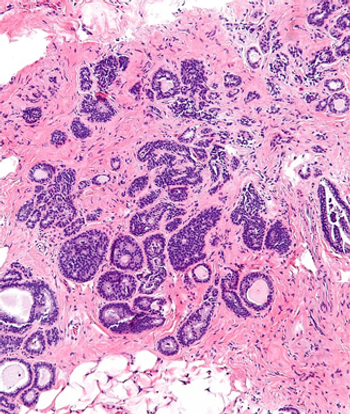

Researchers have identified a group of women with atypical ductal hyperplasia found on biopsy who should be considered to be at low risk for developing cancer.

A new model using only age at biopsy and number of atypia foci could improve absolute breast cancer risk estimates in women with atypical hyperplasia.